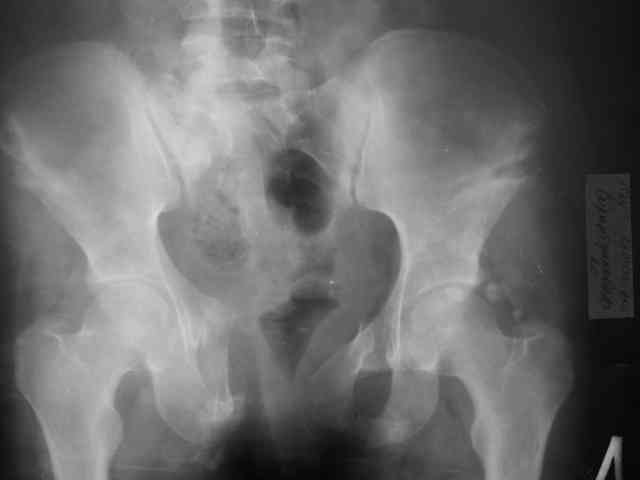

Предоставляю Вашему вниманию неотдаленный результат лечения (5 месяцев) 20 летней девушки с переломом костей таза.

Укорочение левой нижней конечности 2 см.

Снимки в 2 проекциях прилагаются.